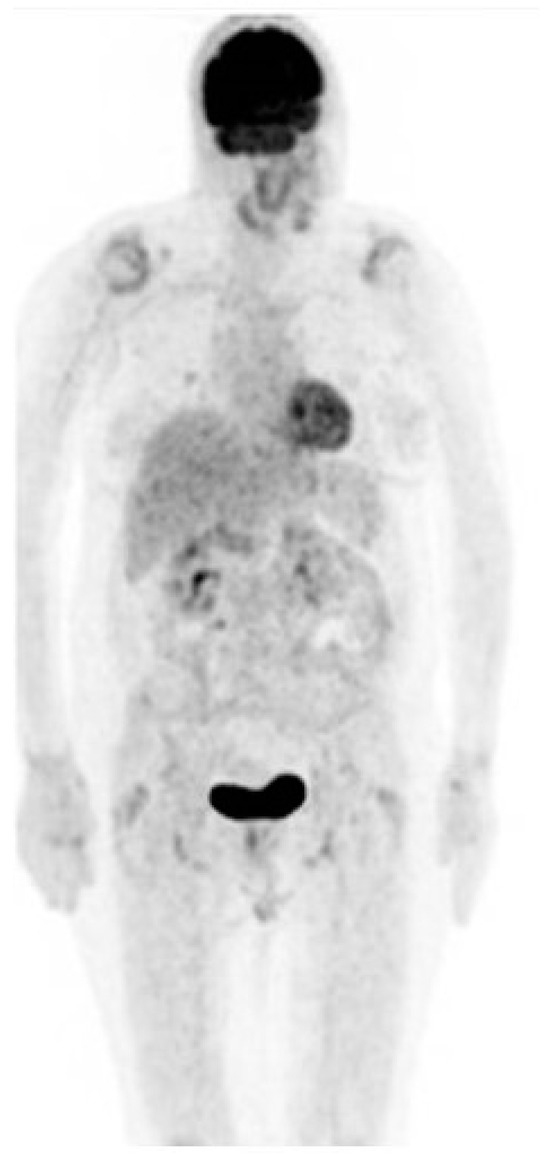

As of August 2023, the patient had received 41 cycles of therapy without adverse effects incidents and a recent PET–CT scan showed a complete response to treatment (Figure 4).

Figure 4. PET–CT scan showing no evidence of disease.